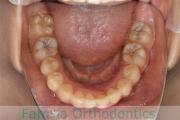

No.22V-029

- 叢生

- 上顎前突

- 19歳

- 男性

- 8448

- FEA 022

- 92万円

でこぼこを治したいということで来院されました。上下左右から親知らずも第一小臼歯も抜歯が必要で、歯科矯正アンカースクリューを併用して大臼歯を後ろに引っ張りながらの治療でした。3年弱、35回程度の通院が必要でした。

叢生が著しく、後戻りのリスクがあります。またアンカースクリューが必須のため、もしもスクリューが安定しないと、治療が難しく長くなってしまう恐れがありましたが、幸い脱落は見られませんでした。

- ≫治療前

上顎

下顎